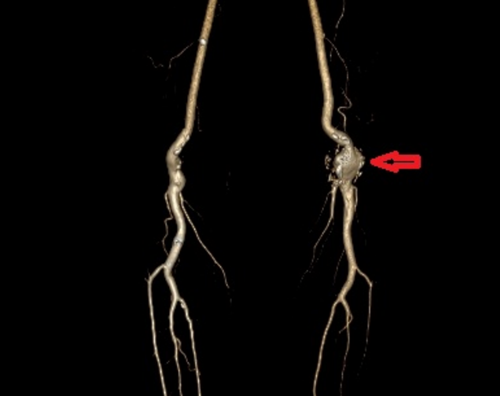

入院后,外周血管介入科主任、主任医师赵扬程详细询问了患者病史并为其进行了全面的体格检查,发现该腘动脉瘤位于左膝盖后方的腘窝处,大小约5 CM×4CM,摸之搏动明显。赵扬程解释,腘动脉位于人体腘窝内,负责向小腿及足部输送血液,腘动脉瘤是由于腘动脉血管壁发生异常扩张,从而形成囊状、球形的病变,并非真正的肿瘤。腘动脉瘤的发病原因尚未清楚,可能由吸烟、外伤、炎症等因素导致血管壁薄弱,动脉在血压的冲击下缓慢发生扩张,从而引起腘动脉瘤。

“该患者患有免疫风湿性疾病多年,手脚多处关节出现变形,腘动脉也存在不同程度的损伤,由此发展形成了腘动脉瘤。”赵扬程表示,当前患者的左侧腘窝处动脉瘤压力过大,破裂出血,致使局部形成的血栓阻塞下肢血流灌注,加上血栓的脱落随时可造成左下肢分支动脉的栓塞,将会严重影响其下肢血供,使患者无法日常活动,更严重的情况是还可造成下肢肌肉组织坏死,有截肢的风险。

由于瘤体正好处于膝关节后,介入手术放置支架容易造成支架移位和折断,患者更适合通过血管外科手术方式达到切除动脉瘤和清除瘤腔中的血栓。赵扬程立刻执行多学科协作诊疗方案,邀请副院长、手足显微外科专家、主任医师刘鸣江,风湿免疫科罗徐医师讨论患者的手术方案。刘鸣江院长结合患者影像学检查,详细询问患者病情,仔细检查患者双下肢动脉搏动,浅表静脉走形,腘动脉瘤病灶等情况,同时考虑到患者体型偏瘦,双下肢浅表静脉细的特点,最终确定最优手术方案。